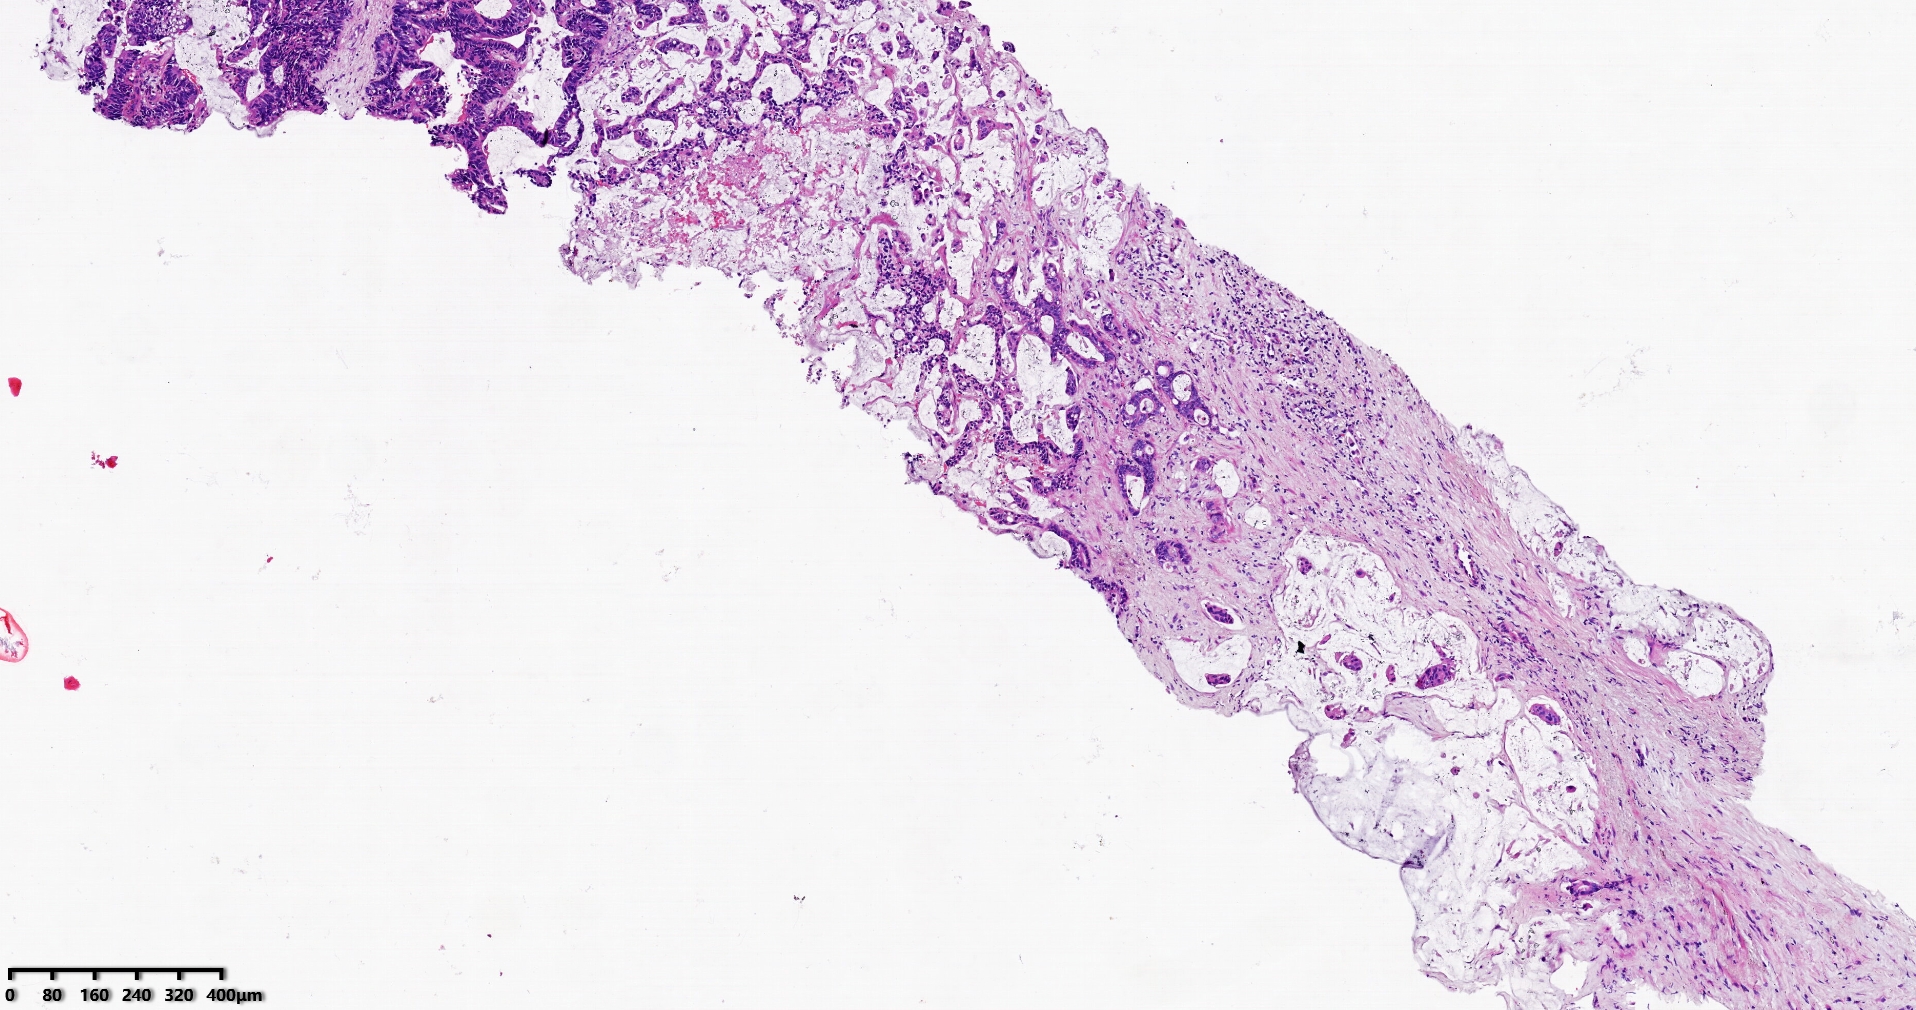

标本名称肝脏穿刺

大体所见灰白灰红色穿刺活检组织两条,长1.7-1.9cm,直径0.1-0.2cm。

考虑符合:肝内胆管癌

考虑转移性黏液腺癌,消化道来源可能,建议做免疫组化,排除胆管源性。